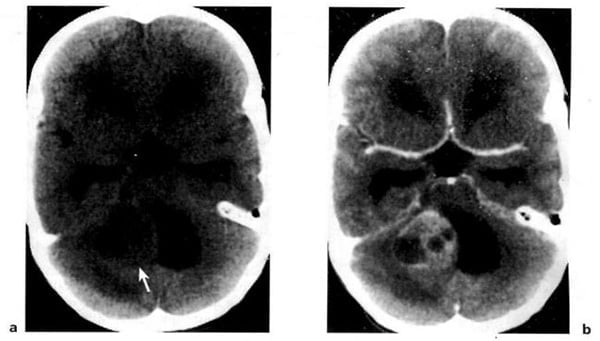

Hình 1.58. U nguyên bào tủy của thùy nhộng tiểu não ở trẻ 2 tuổi. Cắt lớp cách sau 10 tháng. Trước tiêm (a), dấu hiệu mơ hồ (mũi tên). Sau tiêm (b), một phần u bắt chất cản quang mạnh.

Hình 1.60. U nguyên bào mạch. Bệnh nhân nam 33 tuổi có hội chứng von Hippel-Lindau. Trước tiêm (a), tổn thương có mật độ hơi cao ở bán cầu tiểu não bên phải (mũi tên). Nốt u bắt mạnh chất cản quang (b).